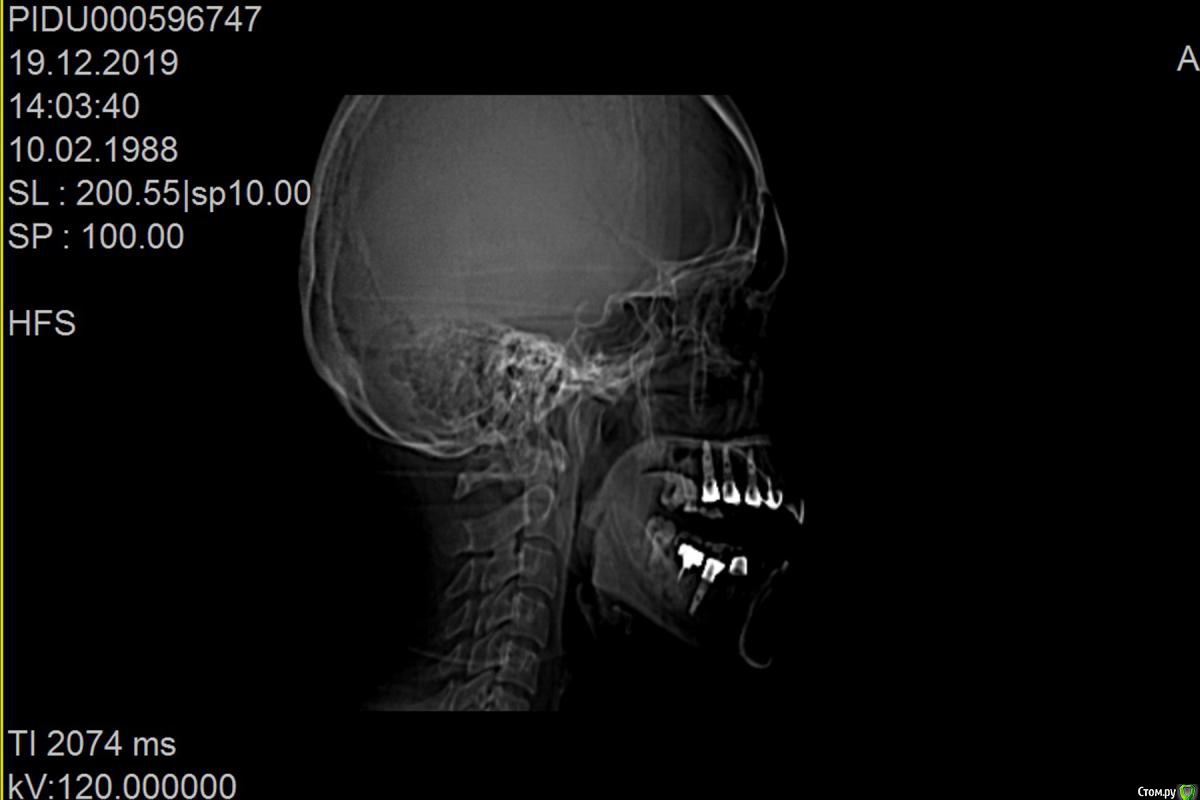

Bier Опубликовано 18 декабря, 2019 Поделиться Опубликовано 18 декабря, 2019 что-то по этому снимку и кости то вокруг имплантатов не видно, очень плохое качество.Сделайте дентальную компьютерную томографию верхней челюсти, чтобы туда вошли пазухи с соустьями.Но что-то мне подсказывает, что там все на удаление. Ссылка на комментарий

irada Опубликовано 21 декабря, 2019 Автор Поделиться Опубликовано 21 декабря, 2019 вот все что у меня есть, один из снимков сделан после 6 месяцев после имплантацииб там где коронок пока нет. дело в том что я студенка я нахожусь в заграницей и моя кт у врача Ссылка на комментарий

irada Опубликовано 21 декабря, 2019 Автор Поделиться Опубликовано 21 декабря, 2019 что-то по этому снимку и кости то вокруг имплантатов не видно, очень плохое качество.Сделайте дентальную компьютерную томографию верхней челюсти, чтобы туда вошли пазухи с соустьями.Но что-то мне подсказывает, что там все на удаление.мне точно пока не могут сказать нужно ли удалять, сказали может придется как то восстанавливать мембрату потому что имлант пробил синус. и что у меня кость гниет. что надо отрезать кусочек корня импланта восттанавливать мембрану. наращивать кость. но при этом не удалять имплант. я просто первый раз о такой операции слышу Ссылка на комментарий

колесников Опубликовано 22 декабря, 2019 Поделиться Опубликовано 22 декабря, 2019 Очень тонкая кость может быть не видна снимке,в том что имплант на снимке выступает в полость пазухи ,ничего криминального нет,итальянские коллеги только так и ставят . То что вам предложили,довольно травматичная операция,необходимо оценить ее целесообразность, Ссылка на комментарий

Bier Опубликовано 24 декабря, 2019 Поделиться Опубликовано 24 декабря, 2019 вот все что у меня есть, один из снимков сделан после 6 месяцев после имплантацииб там где коронок пока нет. дело в том что я студенка я нахожусь в заграницей и моя кт у врачапо этим снимкам криминала нет. Ссылка на комментарий

Bier Опубликовано 24 декабря, 2019 Поделиться Опубликовано 24 декабря, 2019 мне точно пока не могут сказать нужно ли удалять, сказали может придется как то восстанавливать мембрату потому что имлант пробил синус. и что у меня кость гниет. что надо отрезать кусочек корня импланта восттанавливать мембрану. наращивать кость. но при этом не удалять имплант. я просто первый раз о такой операции слышу такую операцию можно сделать. По этому снимку возможно вообще ничего делать не нужно. Нужно посмотреть на КТ. Но повторюсь, ничего криминального нет. Ссылка на комментарий